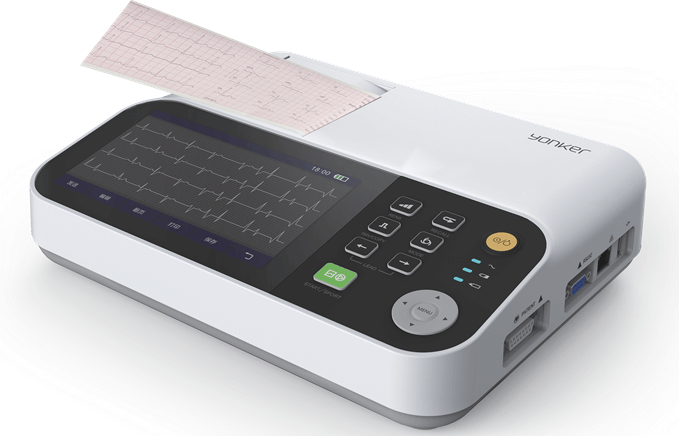

Yonker 7inch display 3 channel ECG Machine with touch screen

Yonker 7inch display 3 channel ECG Machine with touch screen

Yonker 7inch Display 3 Channel ECG Machine With Touch Screen

Yonker 7inch Display 3 Channel ECG Machine With Touch Screen